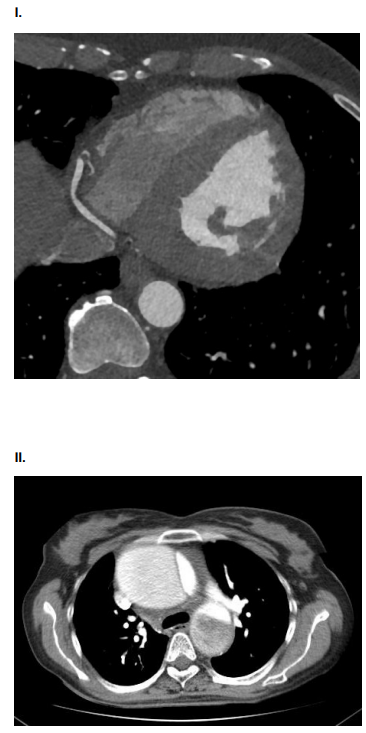

3834589 Ano: 2024

Disciplina: Medicina

Banca: HL

Orgão: Pref. Iturama-MG

Provas:

AMV, 75 anos, tabagista, com queixa de dor torácica súbito, do tipo lancinante. Ao exame físico: Regular estado geral. ACV: RCR em 2T, pulsos radiais assimétricos. PA: 150x80 mmHg. FC 110. Sat O2 90%. Solicitado ECG e Tomografia de Tórax e Abdome com contraste.

Assinale a alternativa que contenha o achado compatível com o quadro clínico da paciente.